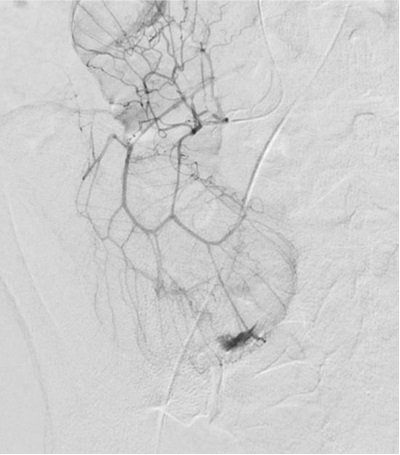

肠系膜上造影

Value of Selective Injection